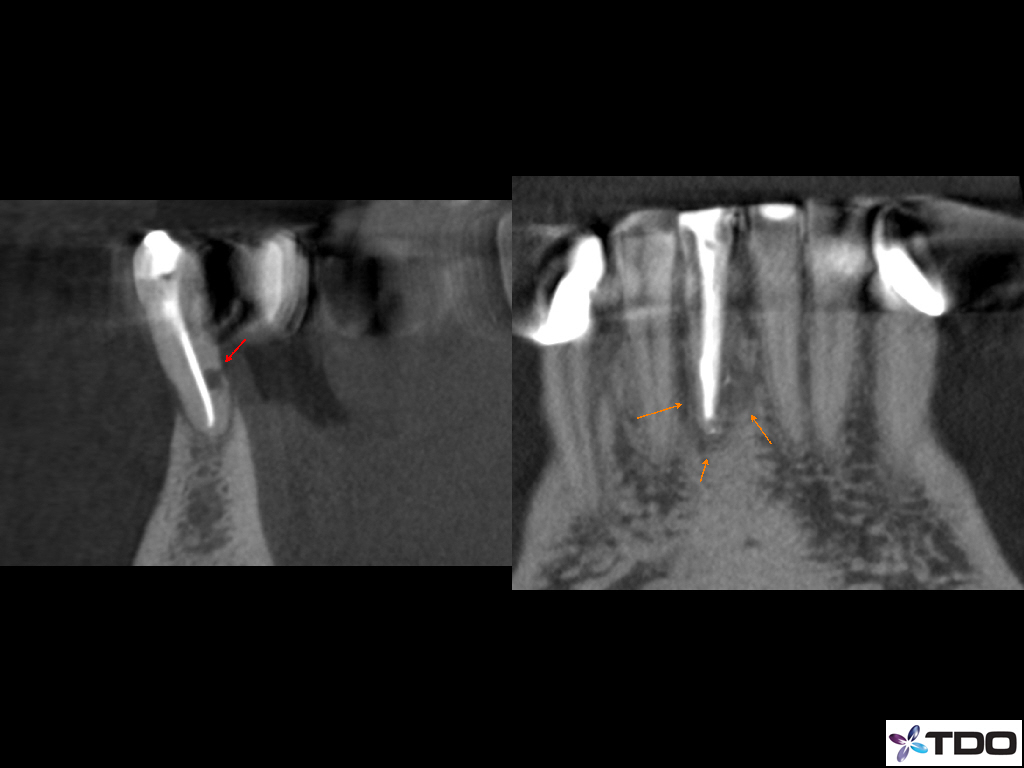

Resorption

Blog Image